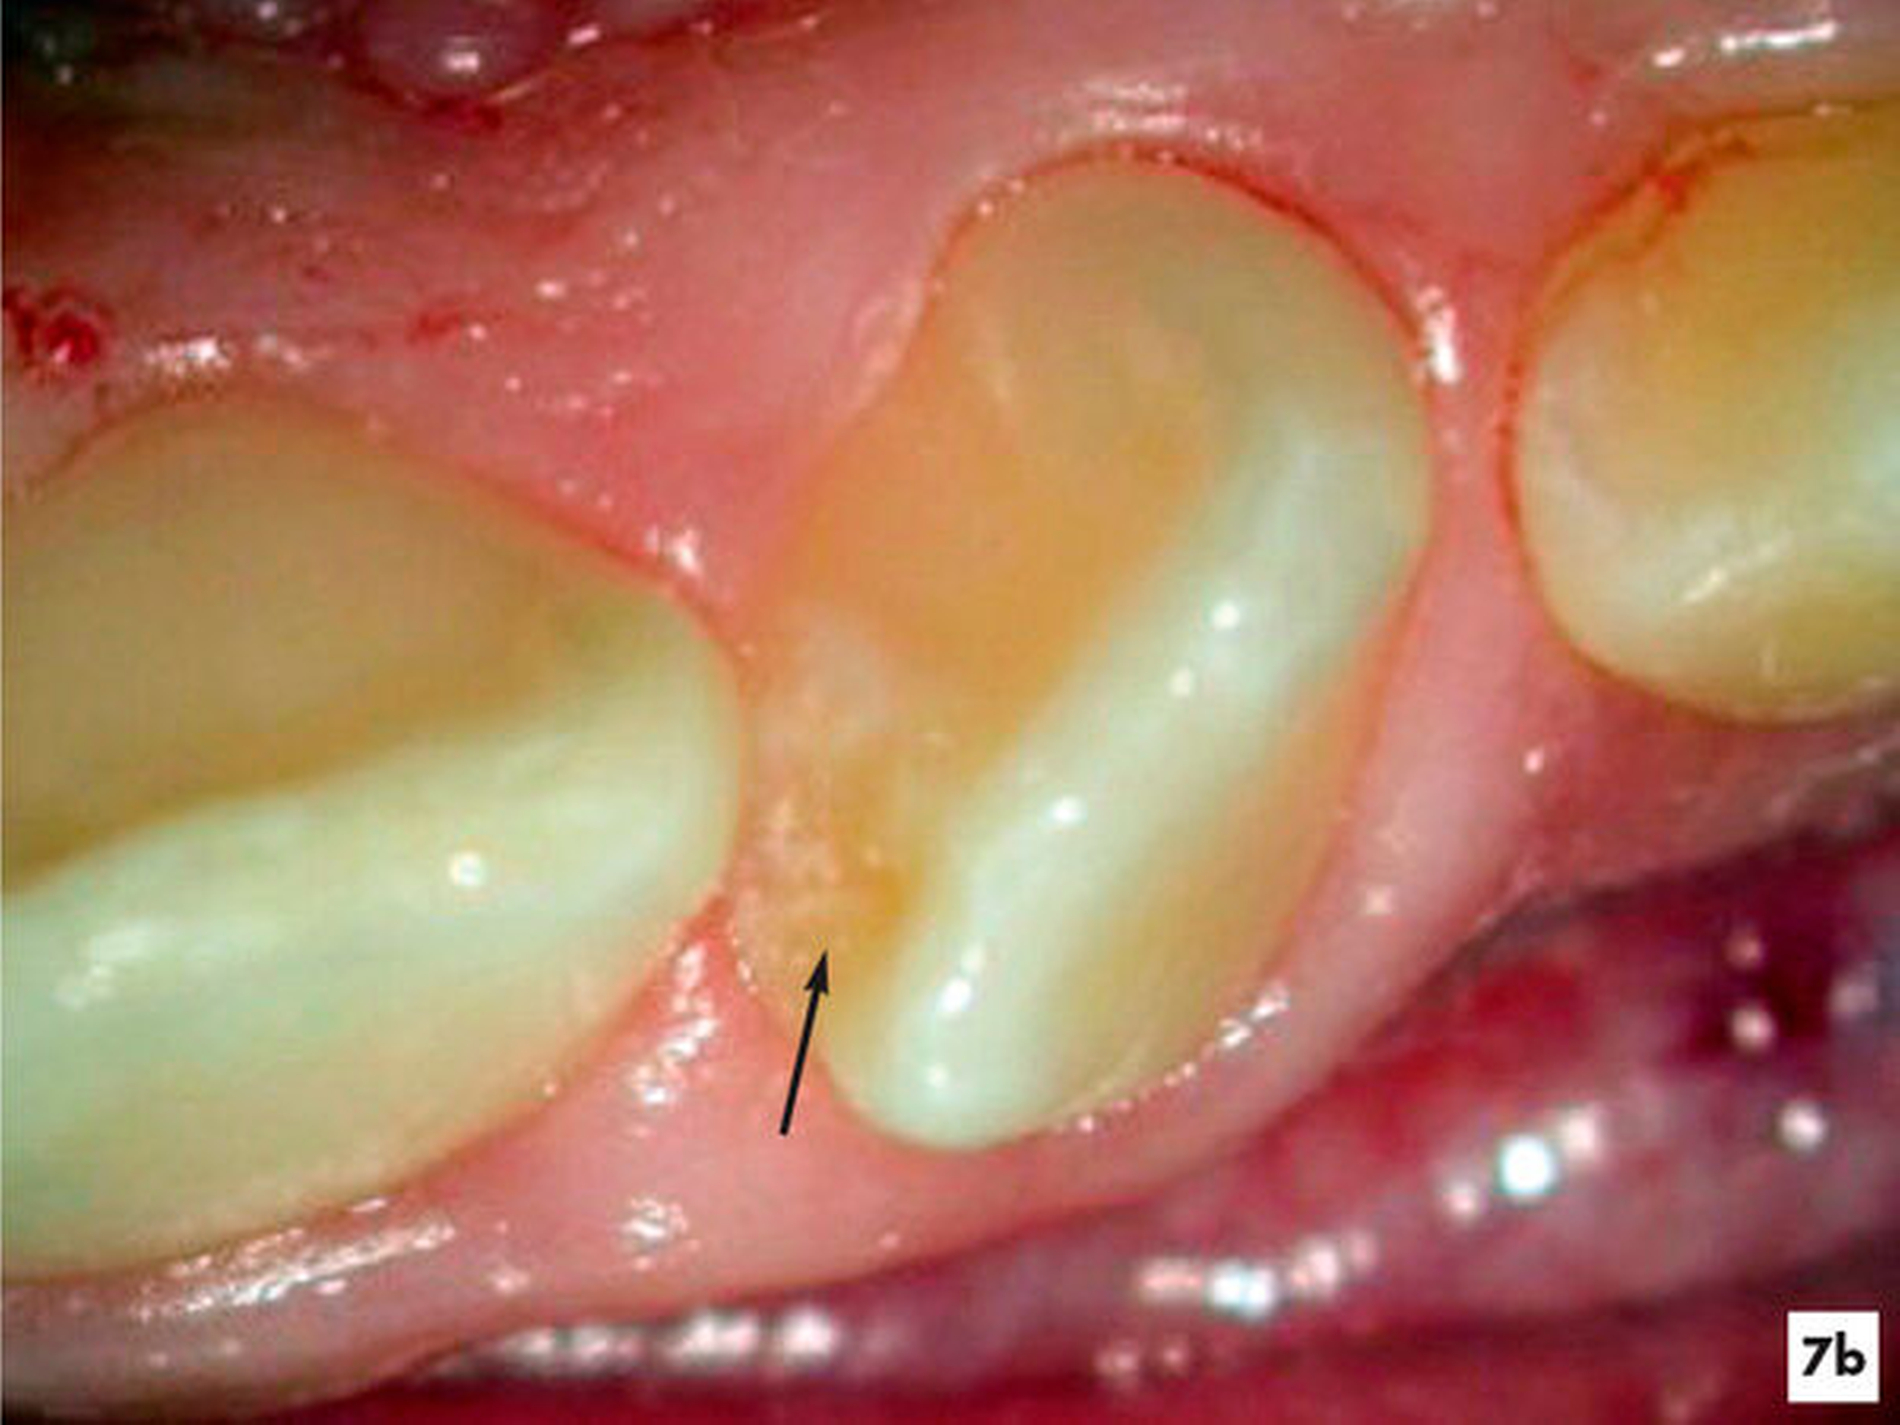

Im Rahmen einer Therapieplanung für eine kieferorthopädische Therapie bei einer elfjährigen Patientin wurde am Zahn 22 eine apikale Aufhellung mit einer hartgewebigen Einstülpung ermittelt. Der Zahn wies keine weiteren pathologischen Befunde auf. Auf den thermischen und elektrischen Sensibilitätstest reagierte die Patientin reproduzierbar positiv. Der radiologische Befund einer apikalen Aufhellung konnte mit der DVT-Aufnahme bestätigt werden (Abbildung 7a). Es lag eine seltene Form eines Dens invaginatus vom Typ 3b nach Oehlers vor.

Unter Sicht mit dem Dentalmikroskop gelang es, den Zugang zur Invagination aufzufinden und minimalinvasiv zu erweitern (Abbildung 7b). Nach einer abschließenden Desinfektion konnte der Hohlraum vollständig mit Guttapercha und einem Epoxidharz-haltigen Sealer verschlossen werden, ohne die Vitalität des Zahnes zu beeinträchtigen. Fünf Jahre nach Abschluss der einzeitigen Wurzelkanalbehandlung reagierte der symptomlose Zahn positiv auf den Sensibilitätstest und die apikale Aufhellung erschien deutlich verkleinert (Abbildungen 7e und 7f).